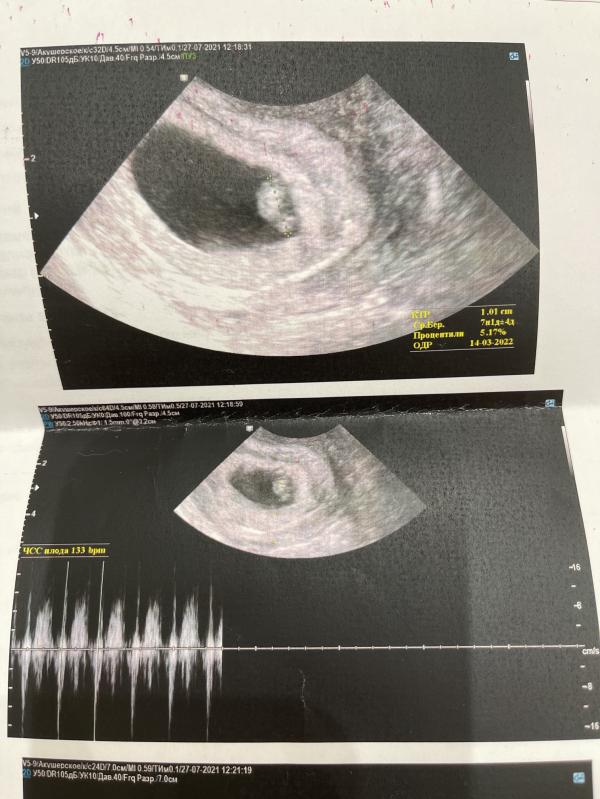

Пока не могу поверить, что это со мной происходит 🙈😅 Из ощущений: хочу только есть и спать) ну, и по всей видимости, на права таки придётся сдать 😅

7 недель по узи, а акушерских 8

Горошинка☺️Это сердечко внизу бьется?

Ага 😊🤍